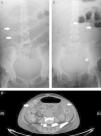

Plain abdominal radiographs were performed where there was evidence of dilated small intestinal loops, indicated by an image of a pile of coins (Panel A), as well as fluid and gas levels and the absence of distal gas (Panel B). Abdominal computed tomography diffusely confirmed small intestinal involvement, with multiple images of “target signs” (Panel C), which reflect swelling of the small intestinal wall, and an increased contrast uptake, with no evidence of intestinal perforation or obstruction, a sign that confirmed suspected lupus mesenteric vasculitis (LMV).

Panel A demonstrates dilated small intestinal loops indicated by a pattern resembling a “pile of coins” (arrows). Panel B shows the fluid gas levels of the intestinal loops (arrows), as well as, the absence of distal gas (asterisk). Panel C shows multiple images of the “target sign” throughout the short intestine.